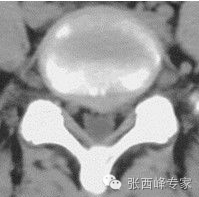

CT腰5骶1椎间盘突出

水平位腰5骶1椎间盘突出